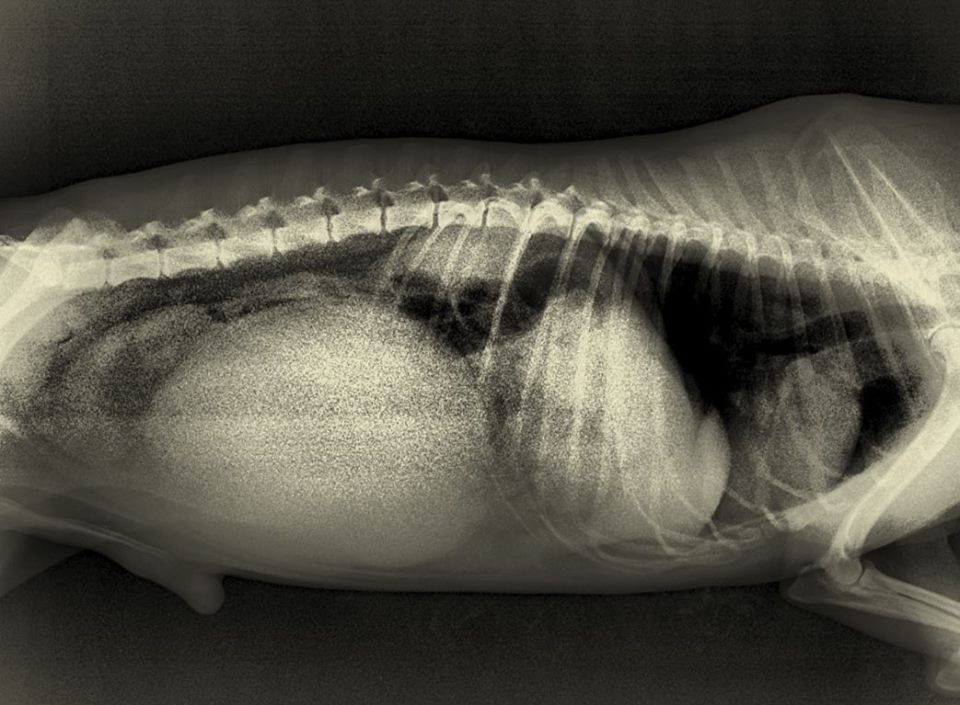

Un médico veterinario revisó radiografías del perro de la raza french poodle y preguntó impactado “¿Dónde le hicieron esto a tu perro?”, según relata Andrés en su publicación.

Botón tenía una enorme protuberancia en el vientre, producto de una golpiza propinada en el Grand Hotel Porto bello.